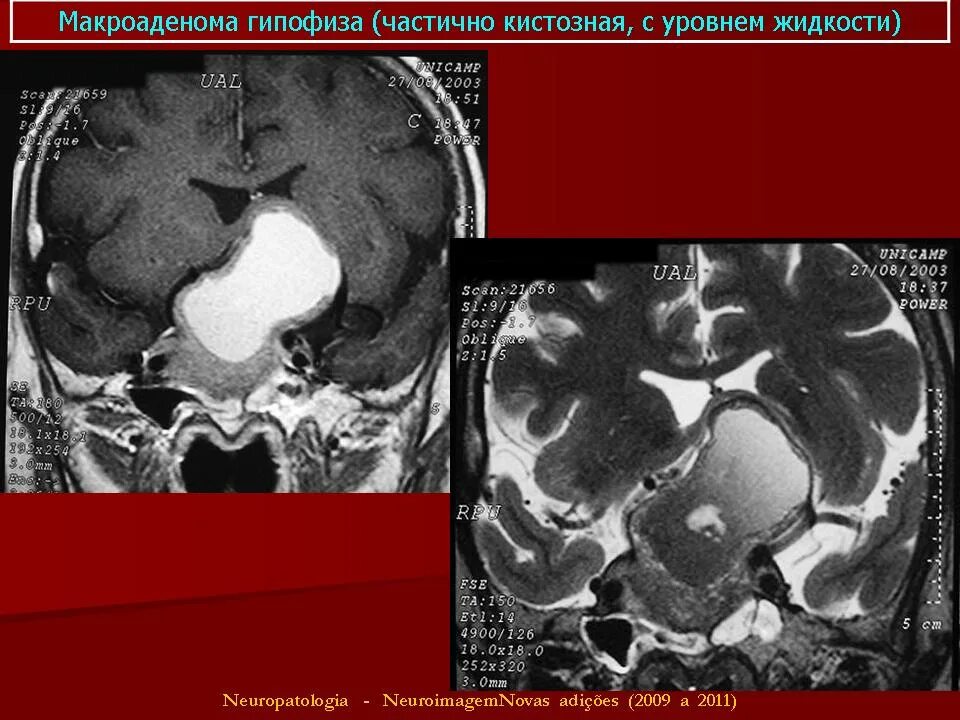

Макроаденома гипофиза